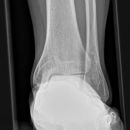

Oberes Sprunggelenk seitlich (2. Ebene)

Technik

• FDA: 1,05 m

• Ausgangsformat: 18/24

• Übertischaufnahme

Indikation

Fraktur, Bandverletzungen, Luxation

Lagerung

liegend auf Tisch

Bein liegt auf der aufzunehmenden Seite

Bein gestreckt, Fuß cranial anziehen (ca. 90° Winkel zum US)

Malleolus medialis und lateralis stehen senkrecht zueinander (C-Griff)

Zentralstrahl

senkrecht

Querzentrierung: Gelenkspalt

Längszentrierung: mittig über Malleolus medialis

Einblendung

proximal 5 QF, lateral 1 QF hinter Ferse

Qualitätskriterien

Oberes und unteres Sprunggelenk rein seitlich abgebildet mit Darstellung auch des Chopartgelenkes und des Calcaneus (Fersenbein). Planparallele Darstellung der Schienbeingelenkfläche und der Talusrolle (keine Doppelkonturen). Die Fibula projiziert sich in das mittlere bis hintere Drittel der Schienbeingelenkfläche.